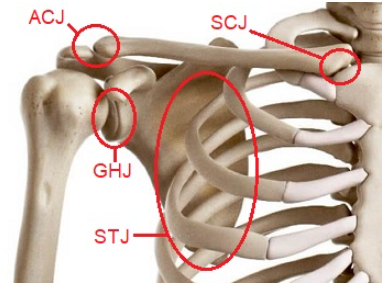

견관절의 구조

견관절은 우리 몸에서 가장 큰 운동범위를 가지고 있는 반면 가장 불안정한 구조를 가집니다.

견관절은 4개의 관절들로 이루어져 있고 서로 상호적인 작용에 의하여 움직임이 일어나는데, 이 때 견관절의 움직임은 견갑골과 함께 이루어집니다.

3개의 해부학적 관절과 1개의 기능적 관절로 나뉩니다.(3개의 해부학적 관절은 SCJ, ACJ, GHJ / 1개의 기능적관절은 STJ)

흉쇄관절, 복장빗장관절(SC joint : SternoClavicular joint)

견쇄관절, 봉우리빗장관절(AC joint : AcromioClavicular joint )

관절와상완관절, 오목위팔관절(GH joint : GlenoHumeral joint)

견흉관절, 어깨가슴관절(ST joint : ScapuloThoracic joint)